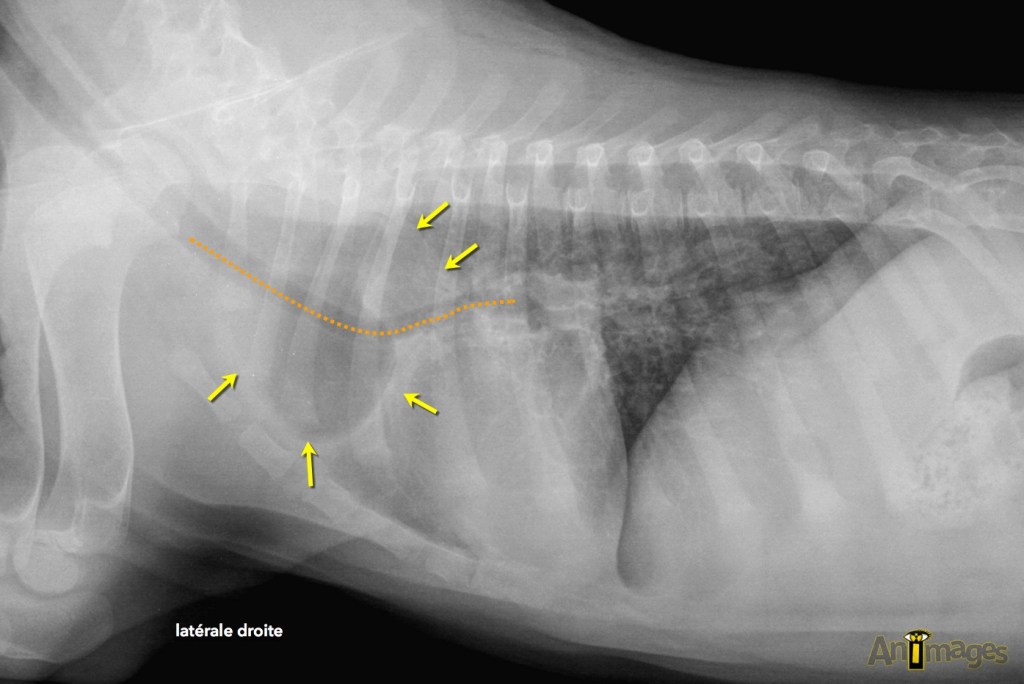

Latérale droite